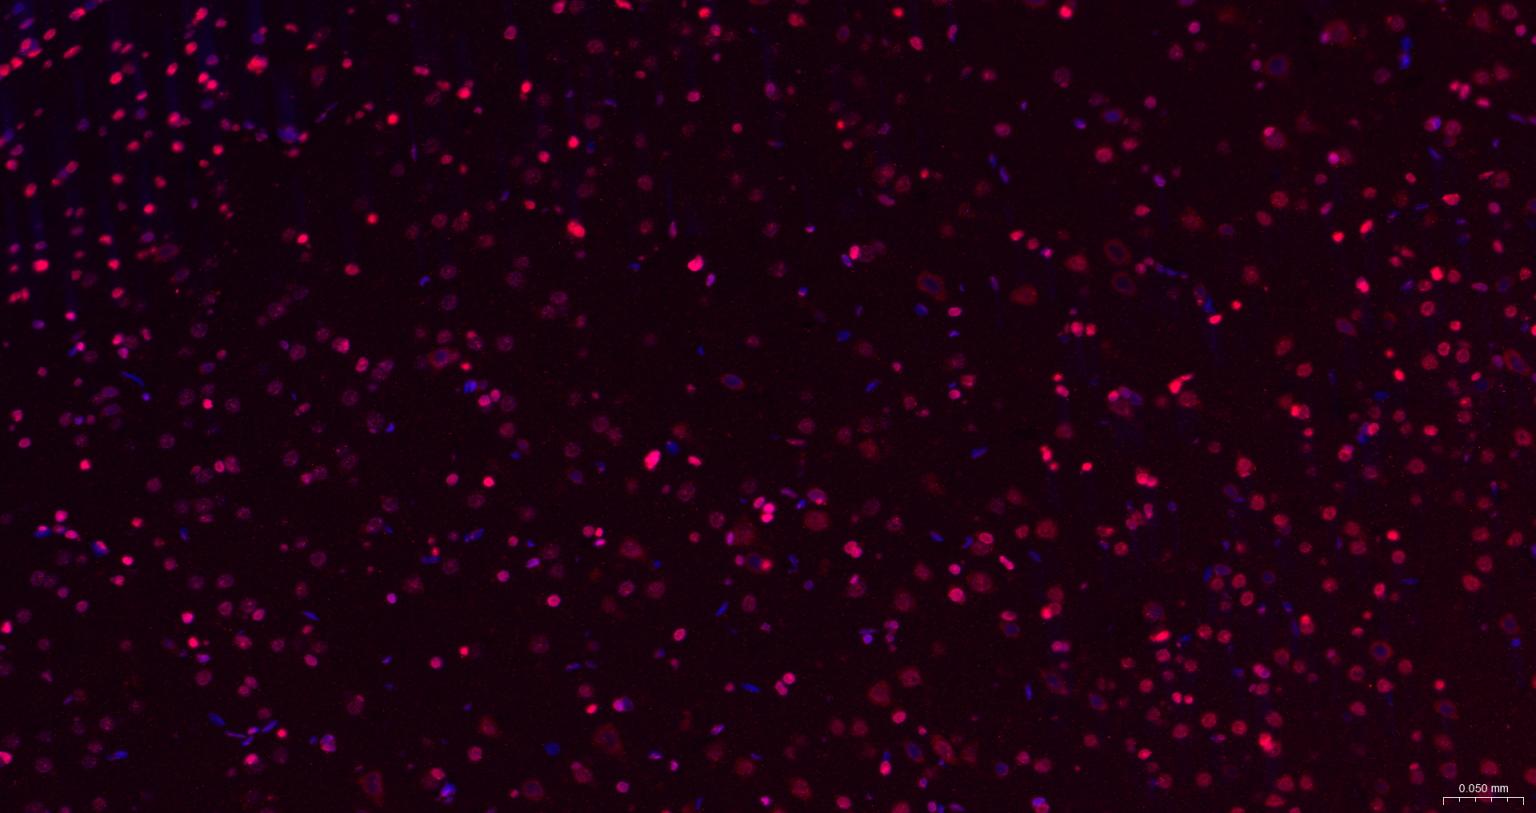

Paraformaldehyde-fixed, paraffin embedded Mouse Cerebrum; Antigen retrieval by boiling in sodium citrate buffer (pH6.0) for 15 min; The section was incubated with CIDEC Polyclonal Antibody, Unconjugated (bs-6796R) at 1:200 overnight at 4°C. Followed by conjugated Goat Anti-Rabbit IgG antibody (Red, bs-0295G-BF594), DAPI (blue, C02-04002) was used to stain the cell nuclei.